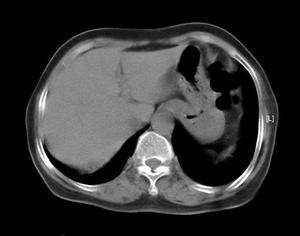

血液白细胞计数及中性粒细胞均显著增加。痰液涂片革兰染色检查,痰培养有助于确定病原体。如为血源性肺脓肿,血培养可发现致病菌。胸部X线检查可见肺野大片浓密阴影其中有脓腔及液平面,或见两肺多发性小脓肿。